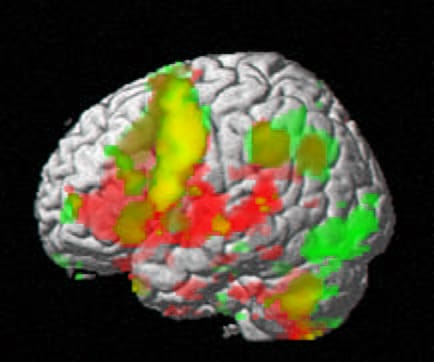

Al cerebro del dolor crónico le han encontrado ya varias singularidades tanto en neuroimagen como en registro de potenciales o cuantificación de neurotransmisores. El cerebro del dolor crónico no es normal. Se entiende que esas anormalidades son consecuencia del impacto continuado del dolor. El dolor acaba dañando el cerebro. Es necesario, por tanto, ganar la batalla de la analgesia con nuevos fármacos. De otro modo se pierde materia gris frontal y engordan las amigdalas.

El dolor crónico, se dice, es una enfermedad y se combate, lógicamente, con analgesia. El dolor crónico lumbar surge de una columna degenerada pero acaba degenerando el cerebro.

– El dolor ya ha dañado el cerebro. Ya nada podemos hacer… Mire: este es un cerebro normal. Compárelo con el de alguien con dolor crónico… por ejemplo, usted…